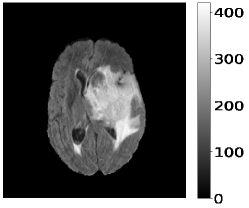

The dataset’s MR images are preprocessed so that the skulls and neck regions are removed. The images are aligned and co-registered to correct any head tilt or mismatches between MR modalities. Each voxel in the image corresponds to of brain tissue. Figure 5 illustrates a 2D axial input MR Images sample and the corresponding ground truth. The input images (a-c) show the different MR modalities: FLAIR, T1CE, and T2 images. The ground truth consists of peritumoral edema (ED) marked in light grey given by an intensity value of , enhancing tumor (ET) represented as a white region with as an intensity value, and the non-enhancing tumor (NET) and necrotic core region (NCR) as dark grey with an intensity value of . The models are evaluated as enhancing tumor (ET), tumor core (TC), and whole tumor (WT). The tumor core corresponds to NET/NCR and the enhancing tumor region. The whole tumor corresponds to all three tumor regions put together. The research aims to learn the ED, NET/NCR, and ET regions.